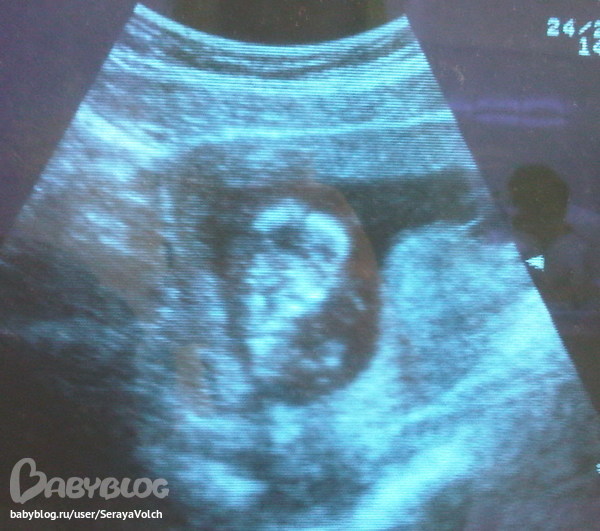

Пронесло, девочки! Все оказалось хорошо - ни тонуса, ни гематомы (тфу тфу!). Рост 66мм, размер соответствует чуть больше 13 неделям беременности - что значит что у меня разница с акушерским сроком.

Прилагаю фотку (сорри за качество, сняла с телефона!). Как видите, ляля решил ради фотосесии "встать" вертикально, и еще палец в рот засунуть

)))